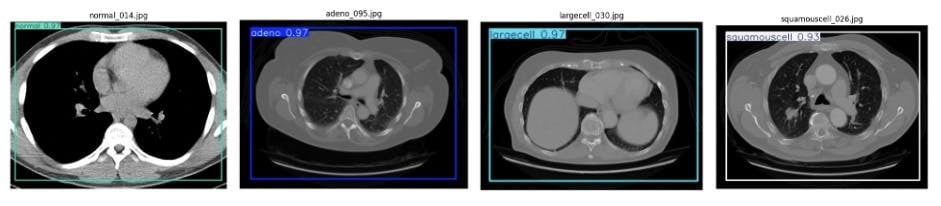

b. 4カテゴリーの物体検出器(胸のCTの病気判定)

c. 4カテゴリーの物体検出器(トウモロコシの病気判定、胸のCTの病気判定)